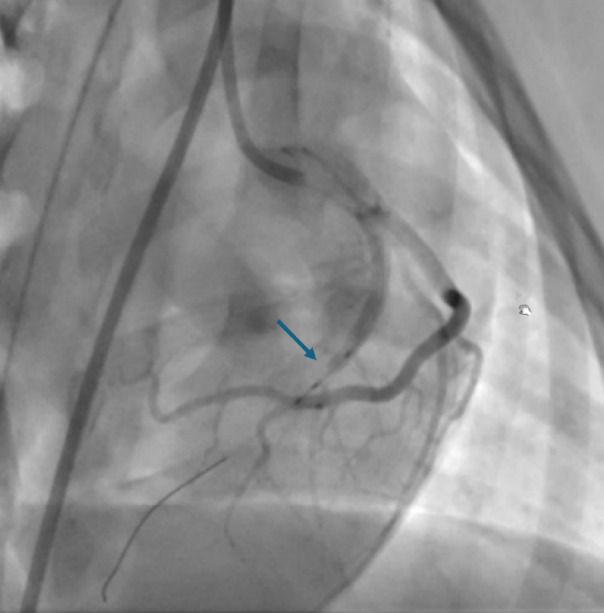

After preparation for general anaesthesia, the minipigs were moved in the Hybrid-Catheter Lab operation room (ACT-Inno AG, Inselspital) and placed on the angiographic table in dorsal recumbency. Right femoral artery was cannulated under ultrasound guidance with a modified Seldinger’s technique. A long 6 French arterial vascular sheath was then inserted in the vessel, and the sheath was sutured. Standard catheter shapes designed for human procedures (for instance, Judkins left and right) were used to allow selective access to the left the coronary artery. A work-horse coronary wire (Hi-Torque balanced Middleweight) was engaged in the distal LAD coronary artery. A balloon was then introduced and inflated in the middle part of the artery, leaving the first diagonal branch (or alternatively the intermediate branch) patent. Complete occlusion of the vessel was confirmed by coronary angiography with injection of contrast medium and the presence of ECG modifications (e.g. ST elevation). The balloon was left inflated for 90 min (ischaemic phase, Fig. 4) and then deflated to allow reperfusion of the LAD. The minipigs were maintained under general anaesthesia for 120 min during the reperfusion phase. Thereafter, all the procedural catheters were removed before recovery.

Fig. 4.

Fluoroscopic image of the heart taken during the procedure. Left anterior descending coronary artery has been occluded with a balloon catheter during the ischaemic phase. Occlusion site is indicated with the blue arrow.